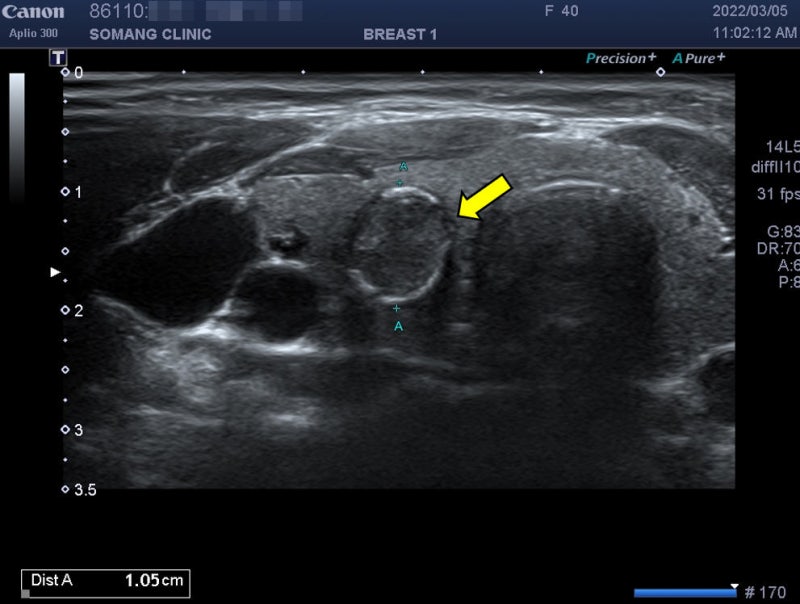

갑상선 석회화 결절의 진단은 갑상선 초음파로 결절의 위치, 개수, 모양, 크기, 내부, 비율, 경계 등을 자세히 관찰하는 것이다. 이로부터 이상이 발견되면 악성의 위험성을 예측할 수 있고 세침흡인세포검사를 시행할 수 있다. 동시에 정상적인 갑상선 기능을 확인하기 위해 혈액 검사를 실시합니다. 그러나 갑상선 초음파에서 갑상선에 석회화된 결절이 보인다고 해서 반드시 갑상선암으로 진행되는 것은 아닙니다. 첫째, 갑상선 결절의 크기가 5mm 이상인 경우 추가 생검이 필요합니다. 그러나 갑상선 석회화가 많이 진행된 경우에는 조직세포 채취에 어려움이 있을 수 있습니다.의정부갑상샘선 김수연유한의원

갑상선 초음파에서 발견된 모든 갑상선 결절이 외과적 제거가 필요한 것은 아닙니다. 갑상선암의 위험이 없는 양성결절이거나 크기가 불확실한 형태의 결절이라면 정기적인 건강관리와 함께 모니터링하면서 6개월 후 갑상선 초음파를 반복하면 진단이 가능하다. 의정부갑상샘한의원 김수연병원은 최고의 장비를 갖추고 있어 당일 검사 한번으로 빠르고 정확하게 진료가 가능합니다. 유방갑상선영상의학과 김수연 원장은 풍부한 경험을 바탕으로 정밀한 검사를 통해 갑상선 석회화 결절을 진단한다. 갑상선 결절이 의심되는 증상이 있으신 분들은 김수연 한의원에 내원하셔서 갑상선 검사를 받으시기 바랍니다.